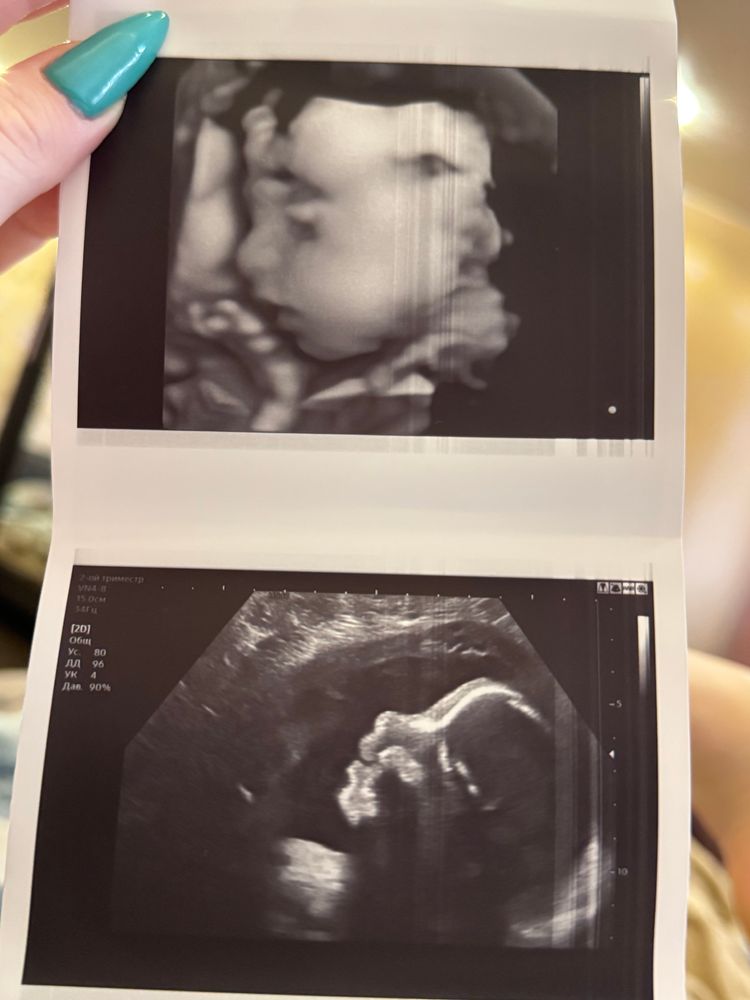

Девочки всем привет. Нет сил моих больше беременность 27 недель, первая долгожданная, все анализы в норме, в том числе узи и скрининг крови. Результаты хромосомных отклонения низкие. В 25 недель ездили с мужем на 3д/4д узи, на фото мне показался очень странный нос, в интернете смотрю 3д фотки других малышей и у всех носики курносые, а у нашего острый. Очень переживаю что это отклонение. Но утешаю себя тем что у меня тоже острая форма носа и он сам по себе не большой. Девочки выручайте у кого было что то подобное. Очень переживаю🥺

У вас на фото ракурс такой, как бы слегка сверху вниз. Меня муж наоборот стебет, что нос курносый у ребенка, у нас у обоих прямые) в профиль очень аккуратный нос у вас!